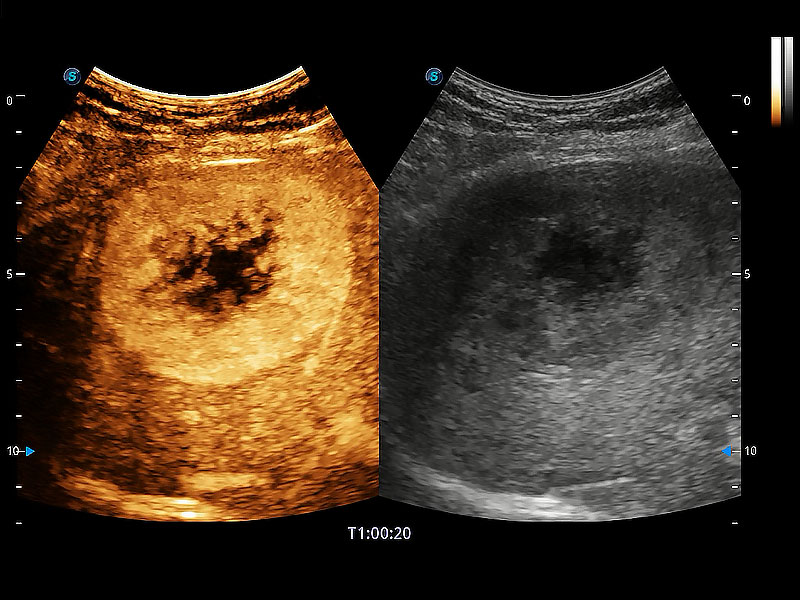

高性能和先进的临床应用工具可以为动物医生提供临床信心。ProPet 80 搭载了先进的腹部和浅表应用工具,帮助医生在日常临床实践中发挥前所未有的作用。

极大提升超低速微细血流的检出能力,同时更精准地滤除软组织和超声信号,为兽用医生提供以往无法通过常规血流获得的疾病诊断信息。

非线性融合造影成像充分利用谐波和基波信号,为难以观察的血流进行增强显像。可用于线阵、凸阵、微凸阵、相控阵探头。